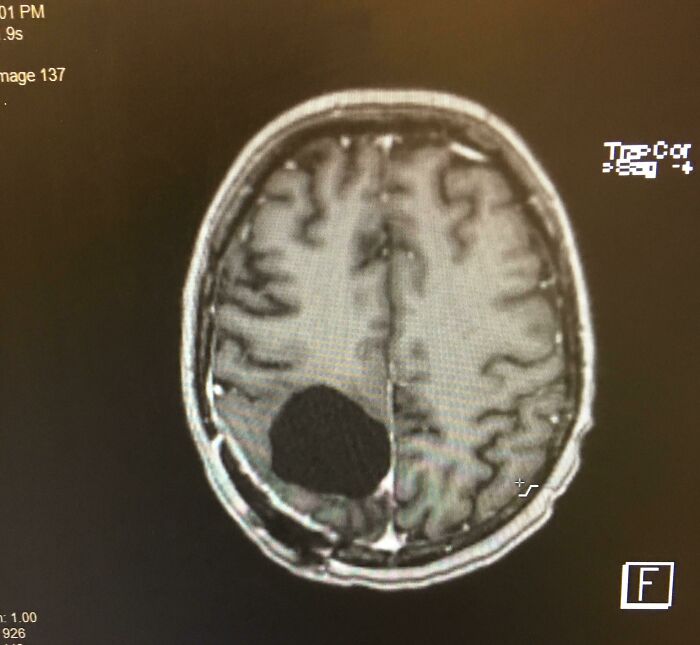

#6 Mal som odstránený nádor na mozgu a teraz som trochu “ľahkomyselný“